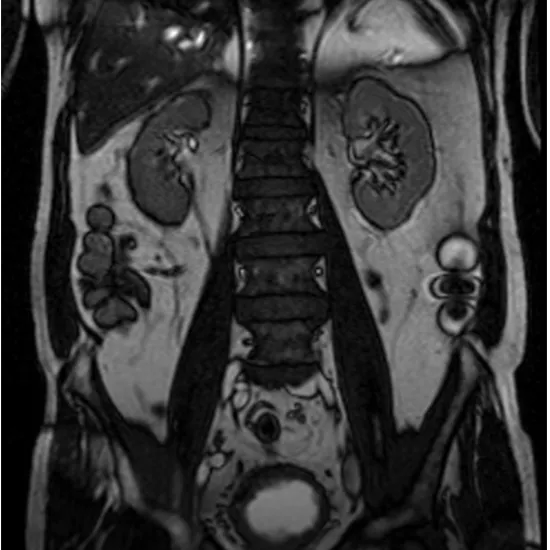

Magnetic resonance is simply referred to as an MRI. Strong radio waves and magnetic fields are used in this clinical scanning procedure to produce detailed images of the urinary system (comprising the kidney, ureter, and bladder). MRI Screening of KUB  helps identify the primary causes of stomach discomfort. This is a great way to gather broad information on someone's urinary tract, including its type, length, and location.